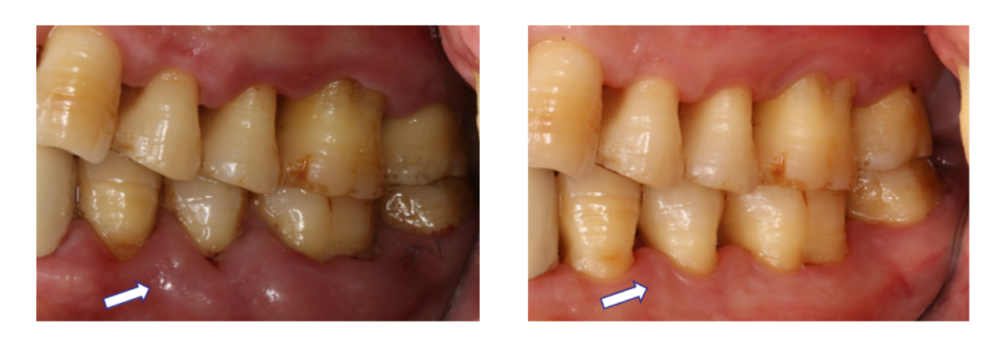

图:治疗前(左)治疗后(右)

完成刮治后,马大叔牙龈的颜色、形态和质地都变得更加健康,不再像“松软的肉袋子”,更有利于清洁,炎症也得到有效抑制。X光片证明他接受牙周基础治疗后,牙槽骨情况也得到很大改善。